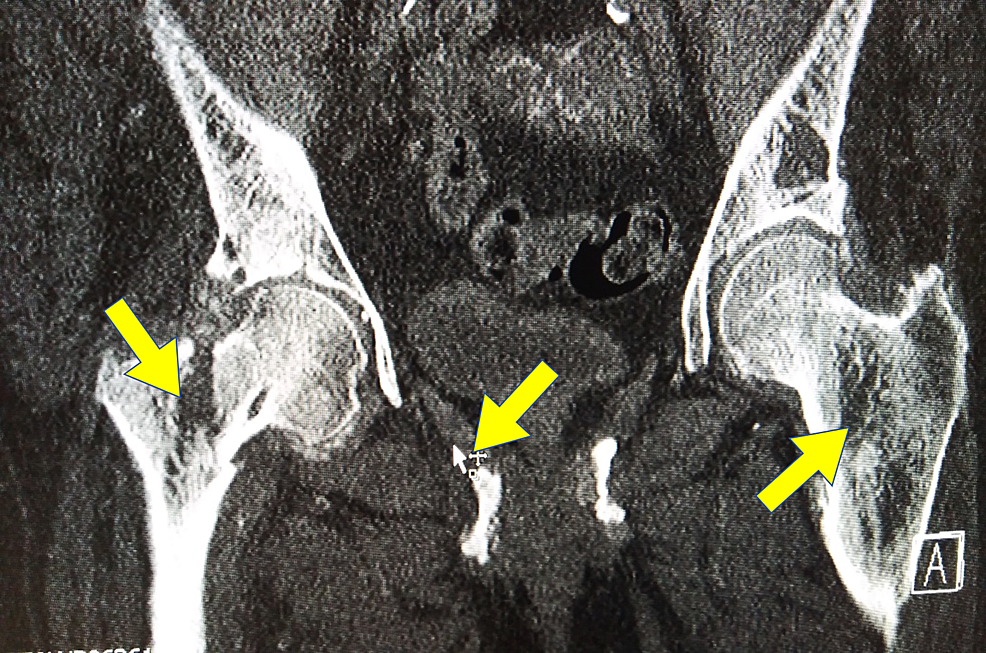

From www.cureus.com

Cureus Hip Fracture in a Patient with Primary Hyperparathyroidism Hip Pain After Parathyroid Surgery Web hungry bone syndrome (hbs) causes persistent low calcium levels in your blood (hypocalcemia). Web how much pain will i feel after my parathyroid surgery? Knee pain, however, is usually not caused by. While patients feel some discomfort after parathyroid surgery, it is quite mild in. Web hyperparathyroidism can cause you to have too much calcium in your blood. Web. Hip Pain After Parathyroid Surgery.